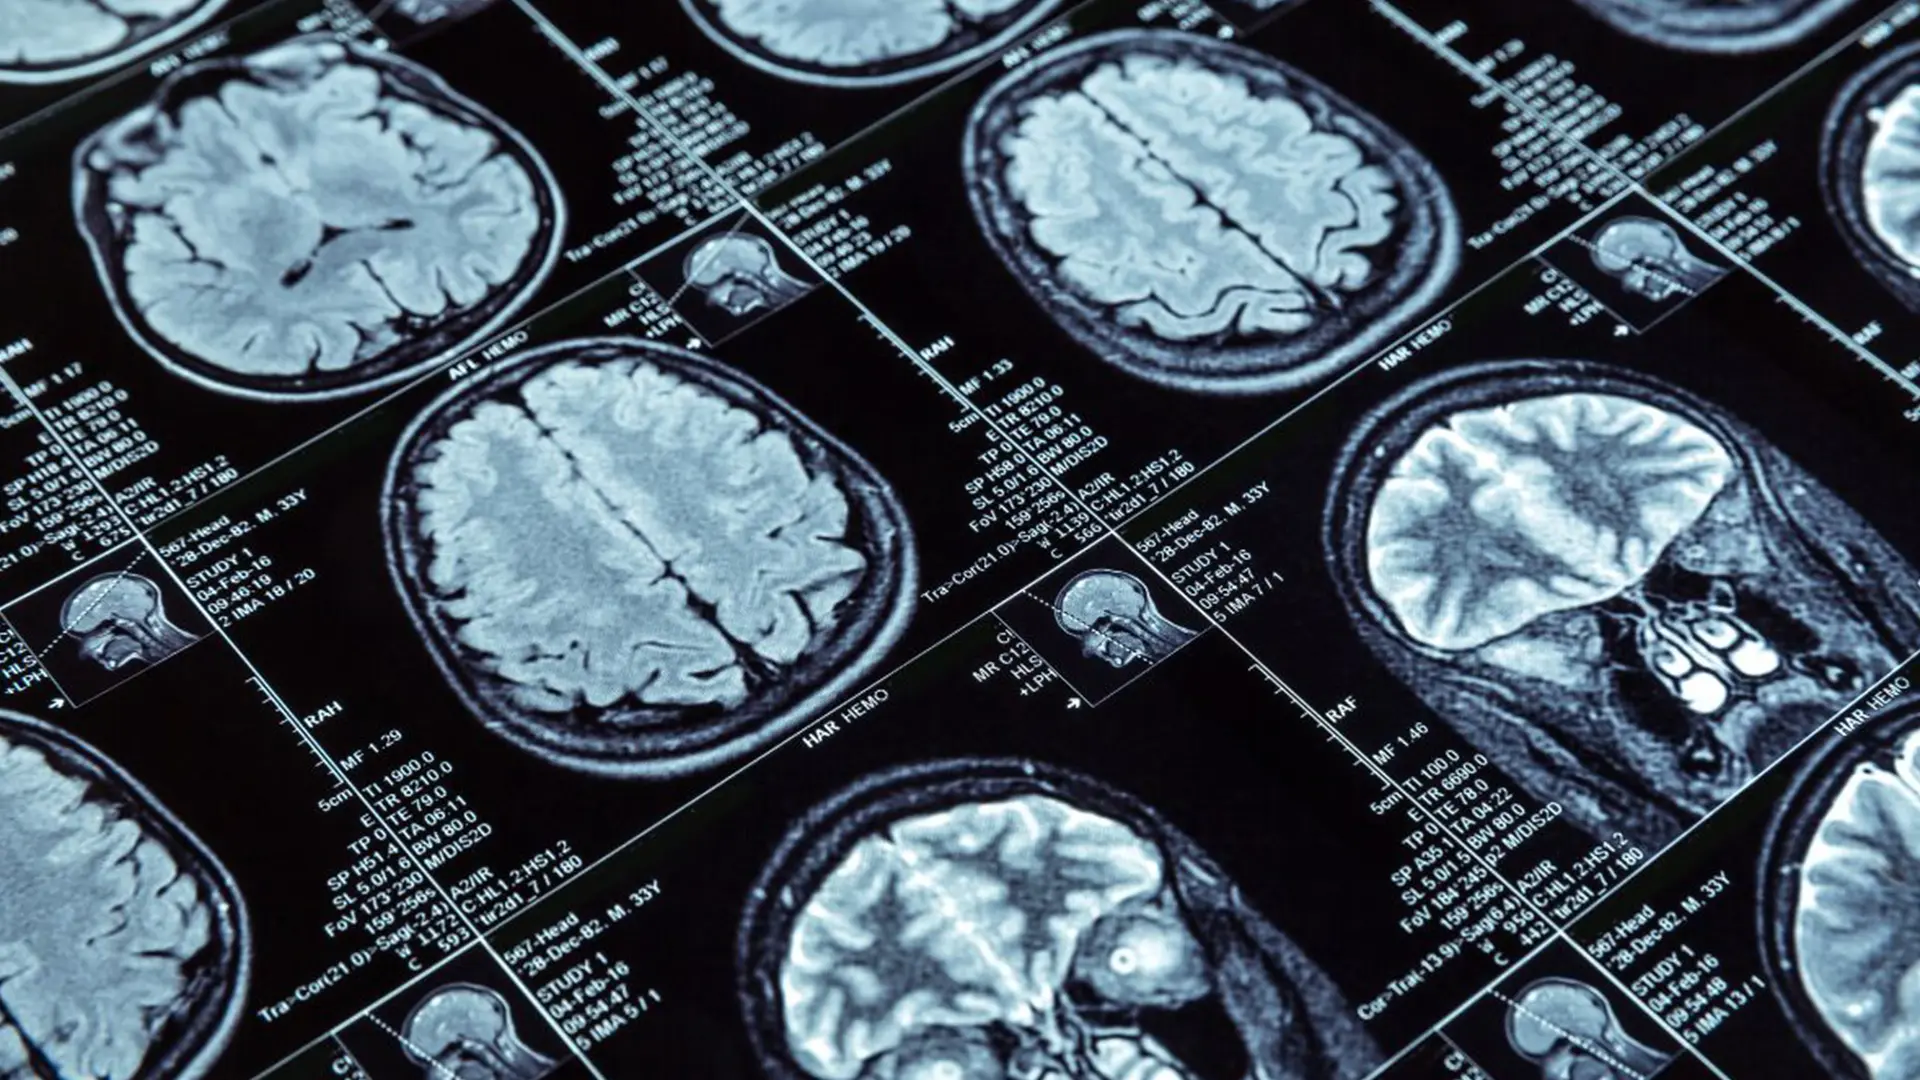

- Segmentazione automatica di tumori cerebrali su immagini RM

- Ottimizzazione per imaging medicale: i modelli sono calibrati su immagini TC, RM, ecografiche ed endoscopiche.

- Ottimizzazione per immagini TC, RM, ecografia ed endoscopia